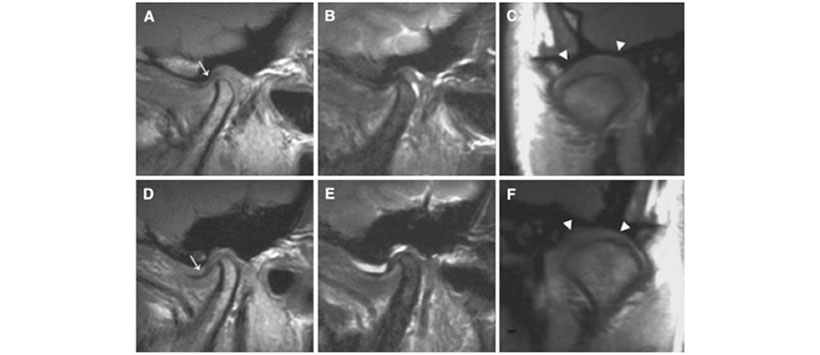

En el primer examen de MRI en la visita inicial (Fig. 1), se observó una ligera erosión del hueso cortical de ambos cóndilos, pero no se observó una deformidad marcada. El disco articular mostró una posición normal en la ATM derecha y desplazamiento anterior en la ATM izquierda. Se observó derrame articular en el espacio articular de la ATM en ambos lados. En las imágenes coronales, se observó proliferación sinovial característica en ambos lados. En el segundo examen de MRI al año después de la visita inicial (Fig. 2), se notó una marcada destrucción del cóndilo y de la fosa articular en la ATM en ambos lados. En las imágenes potenciadas en T2, el proceso condilar que incluye el cóndilo y la fosa articular en ambos lados mostró una alta intensidad de señal, lo que sugiere edema del hueso medular. Tal intensidad de señal alta también se observó en el tejido blando circundante.